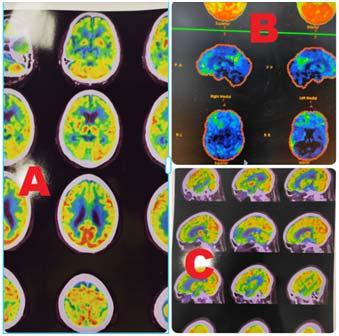

Once Mucormycosis was confirmed, within 72 hours, surgery was performed as well (Fig 2). Post surgery, either Amphotericin B therapy was instituted if it was available and if it was not available then either orally Posaconazole (200 mg q8h) was administered or Isavuconazole at a loading dose of 372 mg orally every 8 hours and maintenance dose of 372mg orally once a day. Inj Amphotericin B was administered at 35 mg/kg. Daily renal function tests had to be performed due to possible nephrotoxicity of Amphoterecin B. Those who could afford, liposomal Amphotericin B injections were given which had lesser renal complications. Alteration in dosage was adjusted according to renal tolerance. Amphotericin B was not available in private clinic/hospitals but only available in government hospitals. Those who were ready to get

Fig 2 — Collage representing resection with debridement of the maxillary lesion and lastly providing an obturator